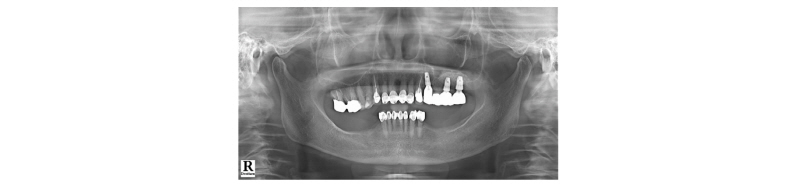

70세의 여자환자로 상악에 사용하던 부분틀니가 불편하다고 호소하시며 내원하였다. 부분 틀니의 지대치인 상악 좌측 견치 또한 보철물 하방으로 우식이 진행되어 보철물 제거후 우식치료 후 보철물을 재제작하여 장착하기로 계획하였다. 치아가 결손되어 있던 상악 좌측 소구치와 대구치 부위는 임플란트 식립(#24i-26i, 27i)을 통한 고정성 보철물 수복을 계획하였다(Fig. 19). 장기간의 부분틀니 장착으로 인해 임플란트 식립 예정 부위의 심한 치조제 흡수가 관찰되었으며 특히 소구치 부위가 가장 흡수 정도가 심하였다(Fig. 20). 전층판막 형성 후 상악 좌측 제 1 소구치 부위는 치조정에서 약 2 mm 정도의 매우 좁은 치조제 폭경이 확인되었다(Fig. 21). 먼저 상악 좌측 제 1 소구치 부위 치조정에 horizontal intraosseous groove를 작게 형성한 후 협측골에 근, 원심 양측에 vertical intraosseous groove를 형성하였다(Fig. 22). Chisel을 이용하여 협측 골판을 조금 확장시킨 다음 spreader drill (RS kit, Dentium, Korea)을 단계적으로 이용하여 충분히 확장시켜 임플란트 식립을 위한 공간을 확보하였다(Fig. 23). 분리된 협,설측 골판 사이 공간으로 Ø4.3 × 10 mm (Implantium, Dentium, Korea) 임플란트를 식립하였다(Fig. 24). 상악 좌측 대구치 부위는 상악동 거상술(측방접근법)을 시행하여 #26i, 27i : Ø4.3 × 10 mm, Ø4.8 × 10 mm (Implantium, Dentium, Korea)를 식립하였다(Fig. 25). 식립된 24i 임플란트와 협,설측 골판 사이의 gap에 합성골 (Osteon II, Xenoss, Korea)을 적용한 다음 협측 골판 상방에 콜라겐함유 합성골(Osteon II Collagen, Xenoss, Korea)을 추가적으로 적용하였고 식립된 26i, 27i 임플란트 부위의 협측골 두께가 얇아서 협측골 상방에도 콜라겐함유 합성골(Osteon II Collagen, Xenoss, Korea)을 적용하였다(Fig. 26). 골이식재 상방에 흡수성 교원질 차폐막(Collagen, Xenoss, Korea)을 피개한 후 감장절개를 통해 장력없이 봉합하였다(Fig. 27, 28). 약 10일 후 발사 시의 임상소견으로 정상적으로 치유가 잘 진행되었다(Fig. 29). 술 후 파노라마 방사선 소견으로 치조제 분할술을 통해 식립된 24i 임플란트와 상악동 거상술(측방접근법)을 시행하여 식립된 26i, 27i 임플란트가 확인되었다(Fig. 30). 4개월 치유 후 이차 수술 시 전층 판막거상 후 협측으로 충분히 증가된 치조제 폭경과 식립된 임플란트 주위에 이식한 골이 혼화되어 치유된 양상이 확인되었고 치유지대주를 연결하였다(Fig. 31). 이차 수술 후 치유가 정상적으로 진행되어 통법에 따라 보철 수복하였다. 보철물 수복 직후 방사선 사진 소견으로 식립된 24i 임플란트의 변연골 위치가 확인되었다(Fig. 32). 보철물 장착 후 1년 후 방사선 소견에서 임플란트 주위 변연골이 안정적으로 잘 유지되고 있었다(Fig. 33). 보철물 장착 4년 후 follow- up 결과 임플란트 주위 치은이 약간 퇴축된 양상을 보였으나 임상적으로 특이한 소견이 관찰되지 않았고 방사선 소견에서 임플란트 주위 변연골이 안정적으로 잘 유지되고 있음을 확인하였다(Fig. 34-36).

|

Fig. 19. First visit. Panoramic x-ray view. |